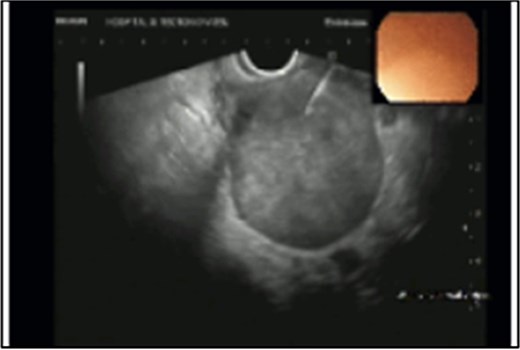

Rectal endoscopic ultrasound revealed an extrinsic lesion on the rectal wall, within the mesorectum (Fig. 4). The biopsy was suggestive of adenocarcinoma.